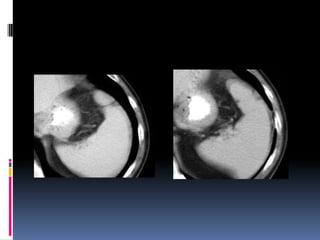

 Segundo órganomas afectado  Lesiones similares a las hepáticas  Sospecha de lesión:  Contornos borrosos  Líquido espacio pararrenal anterior y lateroconal izquierdos  Coágulo centinela

 Pitfalls:  Hendiduras (cleft) congénitos  Artificios de costillas, interfases aire-líquido (estómago, intestino), sondas o catéteres metálicos  Heterogeneidad fase arterial